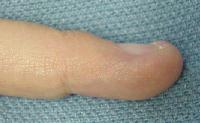

This is the finger of a young woman who had been bothered by a painful fingertip and fingernail, accompanied by a progressive fingernail contour deformity and a pinkish discoloration of the entire proximal nail bed.